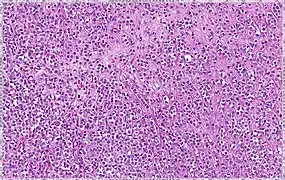

Solid 10% Sheets of classical-appearing cells with little intervening stroma

Alveolar 5% Aggregates of classical-appearing cells

Pleomorphic Classical-appearing but with pleomorphic cells. It may include signet-ring cells, or plasmacytoid cells (pictured) which have abundant cytoplasm and eccentric nuclei.